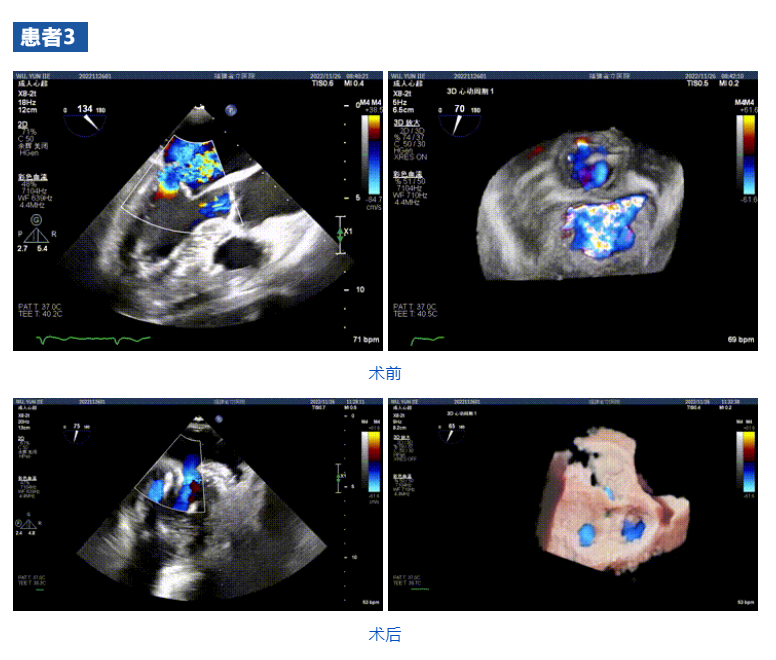

接受治療的三例患者均為器質(zhì)性重度二尖瓣反流(DMR)患者,術(shù)前超聲提示二尖瓣后葉脫垂伴4+反流,左室舒張功能減退。郭延松教授攜同團(tuán)隊成員陳新敬副教授和洪景宣、方明程、楊清勇主治醫(yī)師、心外科丁杭主任以及超聲科賴寶春、葉振盛主治醫(yī)師共同進(jìn)行病情討論。考慮到患者高齡、基礎(chǔ)疾病多、STS評分高,為外科手術(shù)極高危患者,不適合進(jìn)行外科開胸二尖瓣手術(shù),因此決定為患者實施經(jīng)導(dǎo)管緣對緣修復(fù)介入術(shù)(JensClip經(jīng)導(dǎo)管瓣膜夾系統(tǒng))。

在浙江大學(xué)醫(yī)學(xué)院附屬第二醫(yī)院王建安教授團(tuán)隊的支持下,手術(shù)經(jīng)股靜脈-房間隔入路,采用全身麻醉插管,在TEE和DSA引導(dǎo)下完成房間隔穿刺。置入JensClip瓣膜夾系統(tǒng)后,在左房調(diào)整瓣膜夾的位置和軸向,后進(jìn)入左室,在TEE引導(dǎo)下捕捉二尖瓣前后瓣葉,并關(guān)閉瓣膜夾。經(jīng)TEE反復(fù)確認(rèn)手術(shù)效果后最終鎖定并釋放瓣膜夾。術(shù)后即刻超聲顯示瓣膜夾位置穩(wěn)定,功能良好,二尖瓣反流由術(shù)前4+減少至微量,手術(shù)圓滿成功。